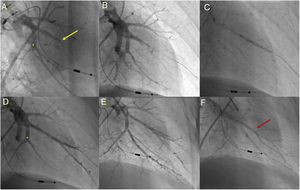

Balloon pulmonary angioplasty techniqueBPA was performed in accordance with the previously published methodology used in our center30 (Figure 1).

Balloon pulmonary angioplasty of segment A7 + 8 of the left lower lobe. (A) Selective pulmonary angiography demonstrating total occlusion of the A8 segment (yellow arrow) and a web at the bifurcation of segment 7 (*); (B) passage of a Whisper MS guidewire (Abbot Vascular, Santa Clara, CA, USA), through the occlusion in segment A8; (C) vessel dilation with a semicompliant 4.0/20 Pantera Pro balloon (Biotronik SE & Co KG, Berlin, Germany); (D) selective pulmonary angiography showing a good final result in segment A8 and segment A7 not yet treated (*); (E) following dilation of segment A7 at the level of the web (*), a good final angiographic result is achieved, with increased arterial flow; (F) venous return observed (red arrow) on final selective angiography of segment A7 + 8 documenting pulmonary flow grade 3.